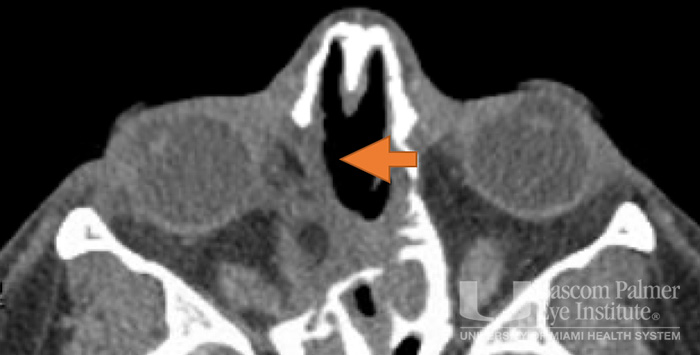

Paralytic and restrictive medial rectus dysfunction secondary to cocaine-induced midline destructive lesions.